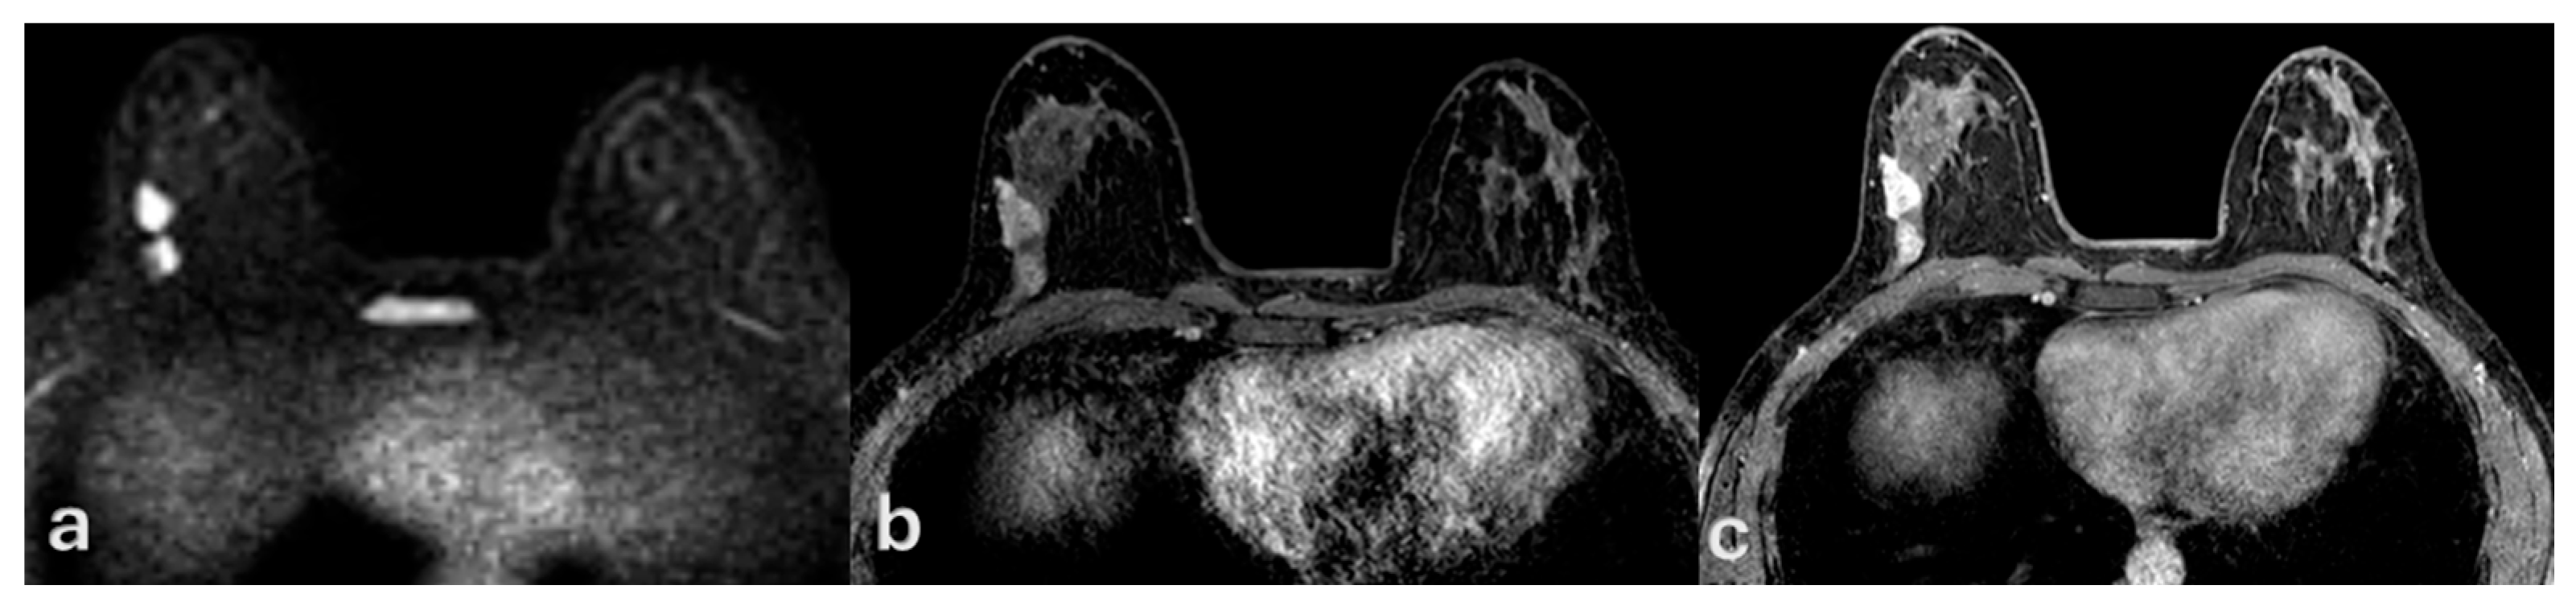

3. Results